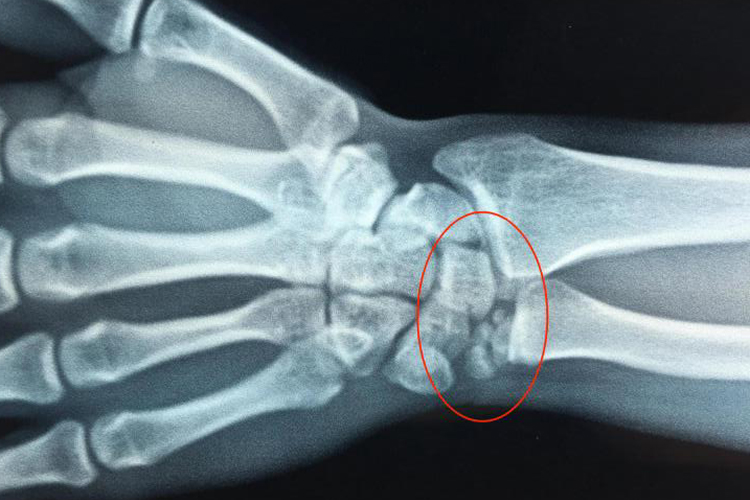

腕三角软骨损伤可出现尺侧腕痛,疼痛常为慢性,伴有腕部无力、酸胀、抓物无力、活动受限和活动疼痛等。患者可发生掌背侧韧带撕裂、尺桡远侧关节脱位,或并发于桡骨远端骨折及腕部的其他损伤。CT和MRI检查可发现三角软骨的缺损、变形或破坏,但有部分的假阴性。